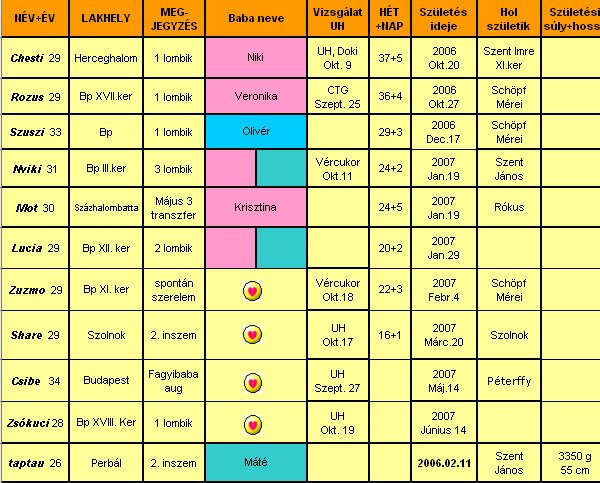

Október 19. UH

Október 19. UH